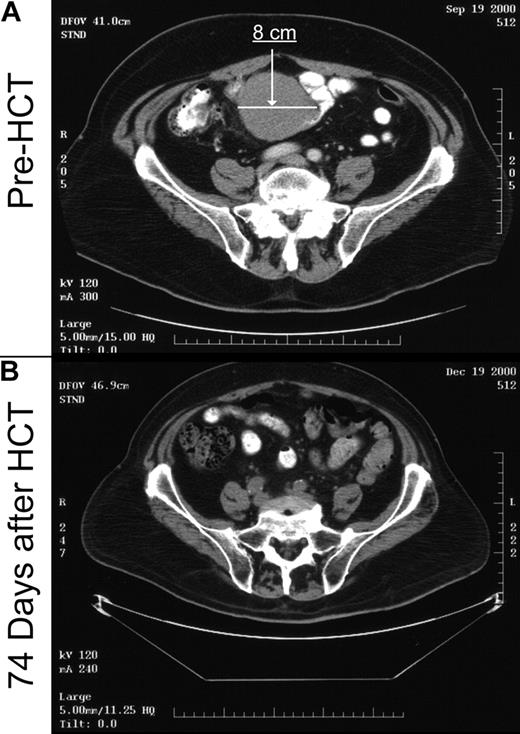

At the time of HCT, 19 patients had measurable disease by CT scan, and one patient had evidence for disease by flow cytometry (Table 3). The disease response rate after transplantation was 85%. An example of an antitumor response after an unrelated donor nonmyeloablative HCT in a heavily pretreated patient with bulky disease who had failed autologous HCT is shown in Figure 2. CR was achieved by 15 patients (75%), including the one with flow cytometry evidence of disease, PR was achieved by 2 patients (10%), and 3 patients (15%) experienced disease progression. The median time to CR was 87 days (range, 21 to 244 days). One of the 15 patients who achieved CR had disease relapse 5 months after HCT, whereas the others have remained in CR. In the time-dependent analysis of the relationship of disease response with GVHD, there was no association between disease response and grades I to IV acute GVHD (P = .36), but a trend was observed with chronic extensive GVHD (P = .09). With an observation time of 24.6 months, all 13 patients who underwent transplantation without evidence of disease have remained in CR. In the patients with progressive disease, one refused further direction or follow-up from the transplant center, one could not have immunosuppression discontinued due to GVHD and concurrent aspergillus infection, and the other 2 had fulminate early lymphoma progression unresponsive to immunosuppression discontinuation. The Kaplan-Meier probability of overall progression-free survival was 60% (95% confidence interval: 43%-78%) at 2 years, and corresponding figures for recipients of related and unrelated grafts were 56% and 66%, respectively (Figure 3). The cumulative probability of relapse at 2 years was 16%. In univariate analysis, the only pretransplantation factor predictive of relapse was the number of preceding treatment regimens. None of 14 patients with less than 4 treatment regimens experienced relapse, compared with 4 of 19 patients with at least 4 regimens (P = .01).

Example of graft-versus-tumor response. Patient no. 20, as shown in Table 1, was a 69-year-old man with rapidly progressive mantle cell NHL. Prior treatments included 8 lines of chemotherapy with only a 6-month remission to high-dose radiolabeled antibodies with autologous peripheral blood stem cell support. At the time of transplantation, he had kinetically failed Etoposide, Methylprednisolone, Ara-C Cisplatin (ESHAP), with rapidly progressive disease during the pretransplantation workup. (A) Pretransplantation computed tomography (CT) scan image (day –27) through the upper pelvis demonstrating an 8-cm by 7-cm mass that extended through twelve 0.5-cm cuts. (B) CT scan image through the same region demonstrating complete resolution of the mass on day +74 after nonmyeloablative transplantation from a matched unrelated donor. The patient remains in remission 30 months after transplantation with no evidence of GVHD.